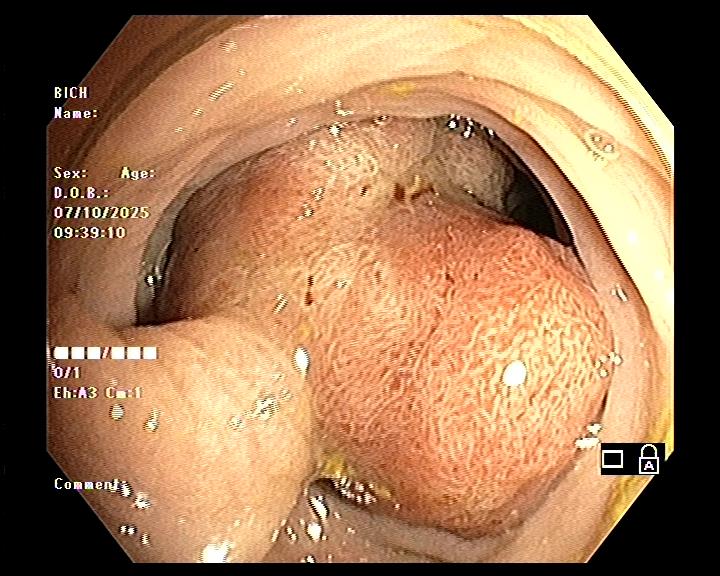

- Trên nội soi: polyp thường có hình chùm nho, niêm mạc nhẵn, dễ chảy máu.

Polyp Peutz–Jeghers là dạng polyp hamartomatous, cấu trúc mô học gồm các tuyến ruột được bao quanh bởi các bó cơ trơn phát triển bất thường.